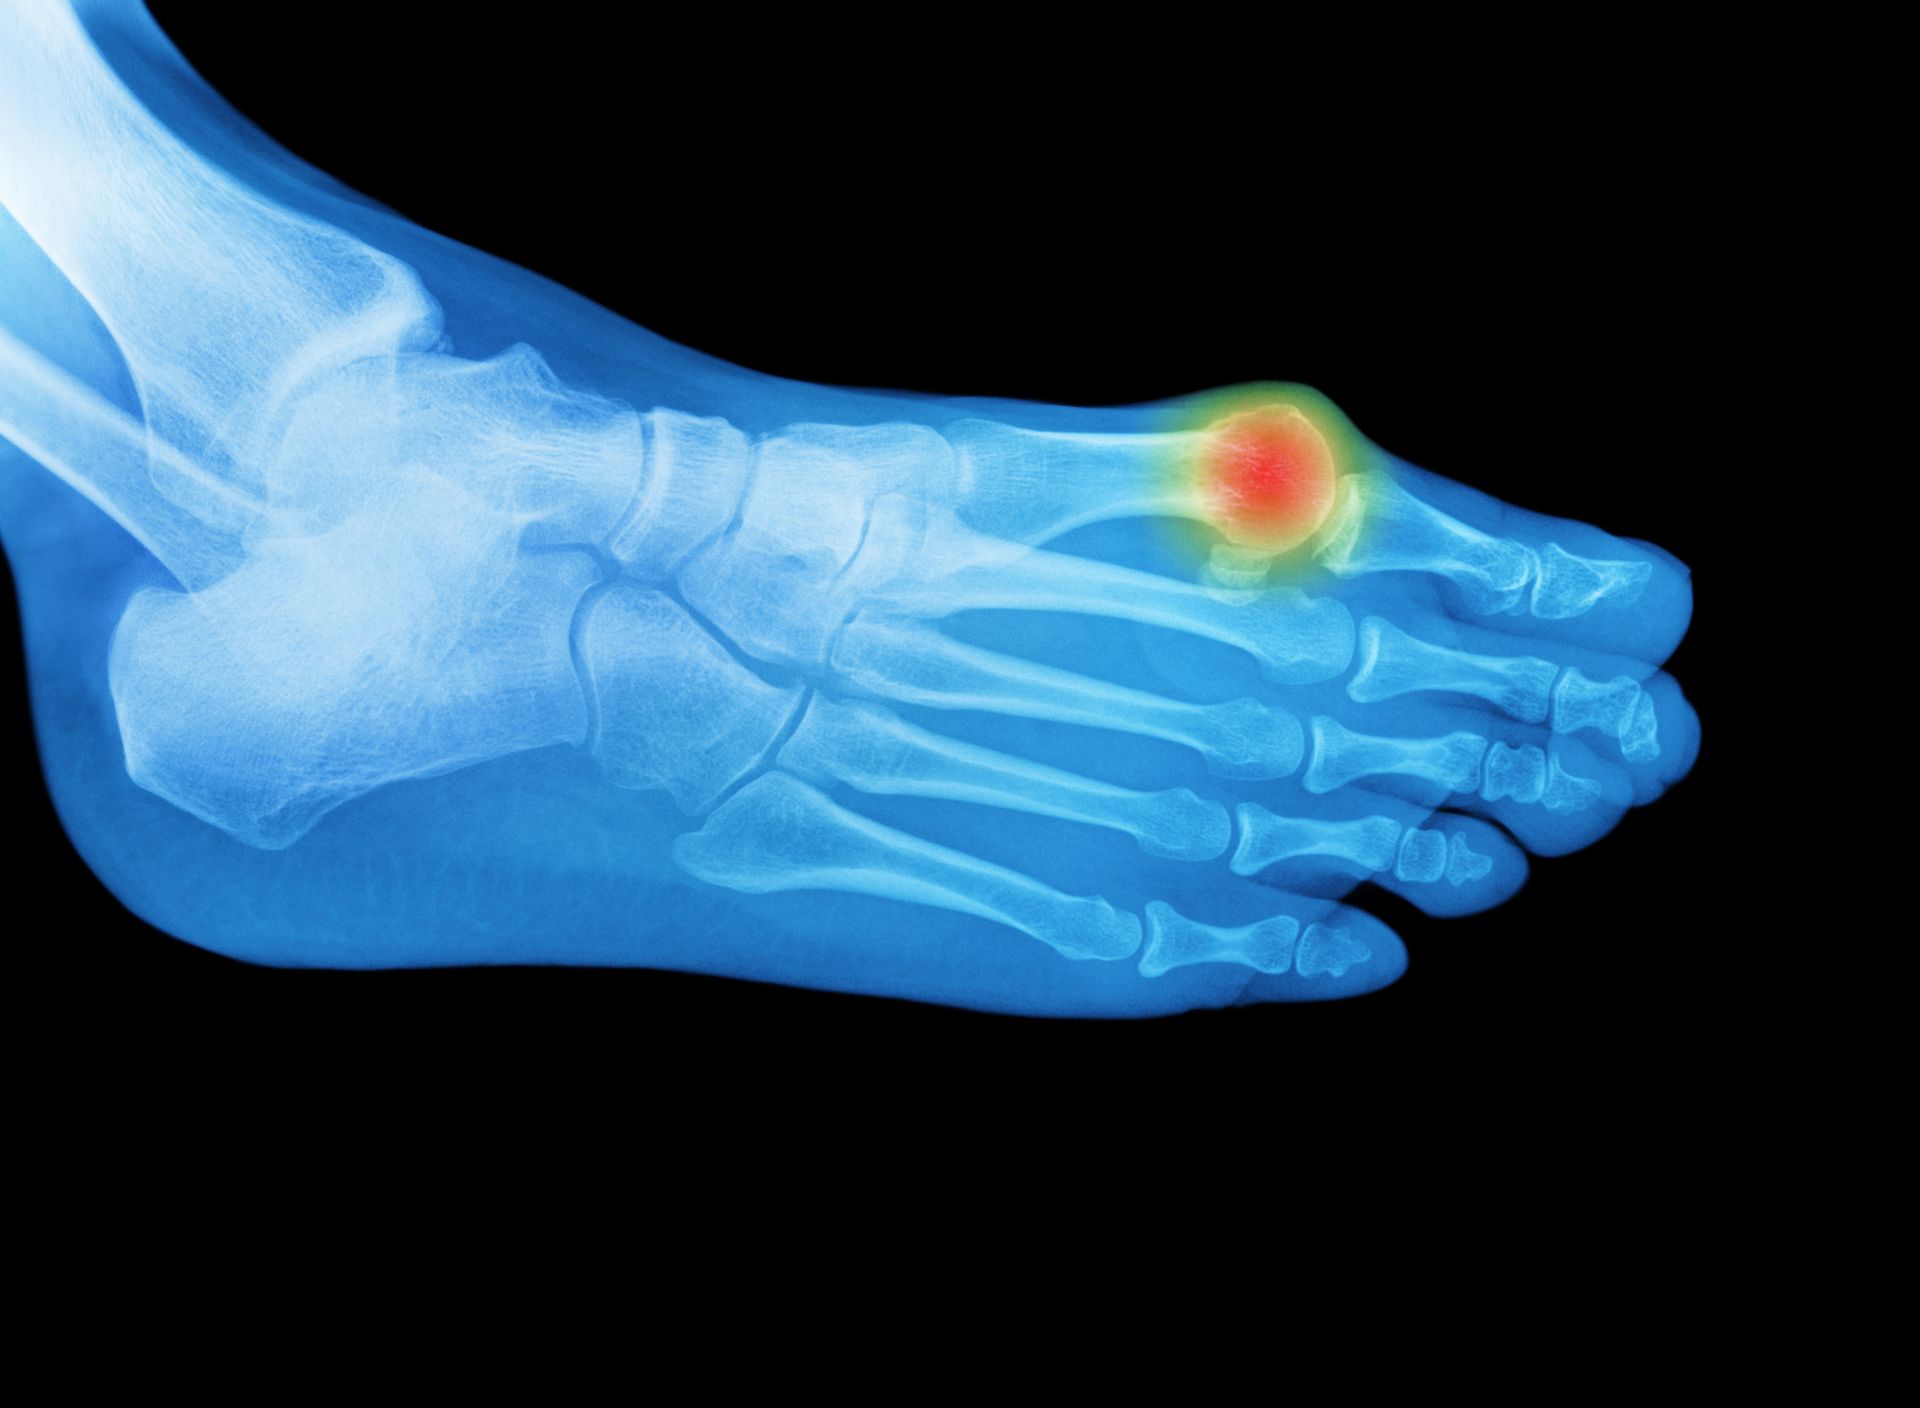

L'alluce valgo è una patologia comune del piede, caratterizzata dalla deviazione mediale del primo metatarso e dallo spostamento verso l'esterno dell'alluce, che nei casi gravi può anche ruotarsi. Questa condizione provoca la deviazione della punta dell'alluce verso le altre dita e la formazione di una prominenza ossea, accompagnata da un allargamento dei tessuti molli. Il dolore associato può essere intenso e limitare la capacità di movimento dell'alluce, rendendo difficile indossare calzature chiuse e camminare senza plantari o scarpe su misura. Nei casi severi, si può osservare un conflitto doloroso tra l'alluce e il secondo dito, spesso accompagnato da un’alterata sensibilità dell'alluce, specialmente in sede dorsale.

La diagnosi di alluce valgo è prevalentemente clinica, basata sui sintomi di deformità e dolore all'avampiede riportati dal paziente. Tuttavia, per una valutazione più approfondita, si utilizzano radiografie in ortostasi del piede per determinare il grado di valgismo e altre eventuali deformità associate. In alcuni casi, come sospetta degenerazione dell'articolazione metatarso-falangea o infiammazione dei tessuti molli, può essere necessaria una risonanza magnetica. Strumenti diagnostici come la baropodometria e la gait analysis sono utili per studiare le alterazioni biomeccaniche in posizione eretta o durante il cammino, fornendo una visione completa delle problematiche funzionali del piede.